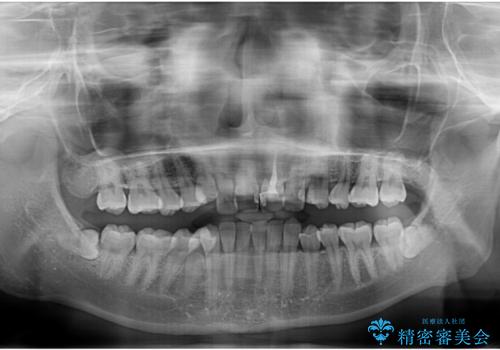

- 上下の前歯のデコボコを改善したいと来院された患者様です。

上顎の歯列幅が狭く、それによって歯が並ぶスペースが不足しています。

また下顎の歯列幅も制限され、内側に歯が倒れています。

左上の乳犬歯は当初保存する計画でしたが、虫歯が大きいため抜歯になり、患者様の希望によりブリッジにしました。